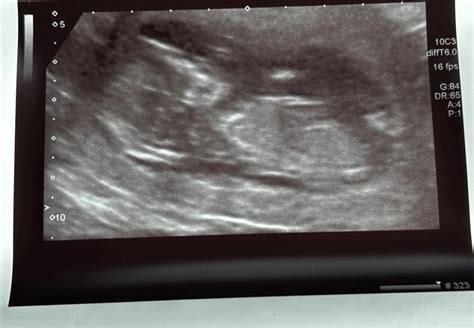

So, what exactly is this 20-week anatomy scan? Simply put, it’s a detailed ultrasound conducted, usually, between 18 and 22 weeks of pregnancy. The sonographer will be checking your baby from head to toe (literally!), looking at all the major organs and body parts. This includes the brain, heart, spine, kidneys, limbs, and more. They’re also assessing the placenta, amniotic fluid, and your uterus to make sure everything looks healthy. The goal is to identify any potential structural abnormalities or issues early on. It’s a comprehensive check-up for your little one before they make their grand entrance into the world. During the scan, the sonographer will be taking measurements and documenting what they see. This information is then used to assess the baby’s growth and development. The scan itself typically takes about 30 to 60 minutes, and you’ll likely get to see some amazing images of your baby. Many parents find this to be an incredibly emotional and heartwarming experience, getting that first real glimpse of their growing child. But again, it’s totally okay to feel a bit anxious! The medical professionals are highly trained to perform these scans, and they’re there to provide you with support and answer your questions. This scan isn’t just about looking for problems; it’s also about celebrating the miracle of life and the amazing process of pregnancy.